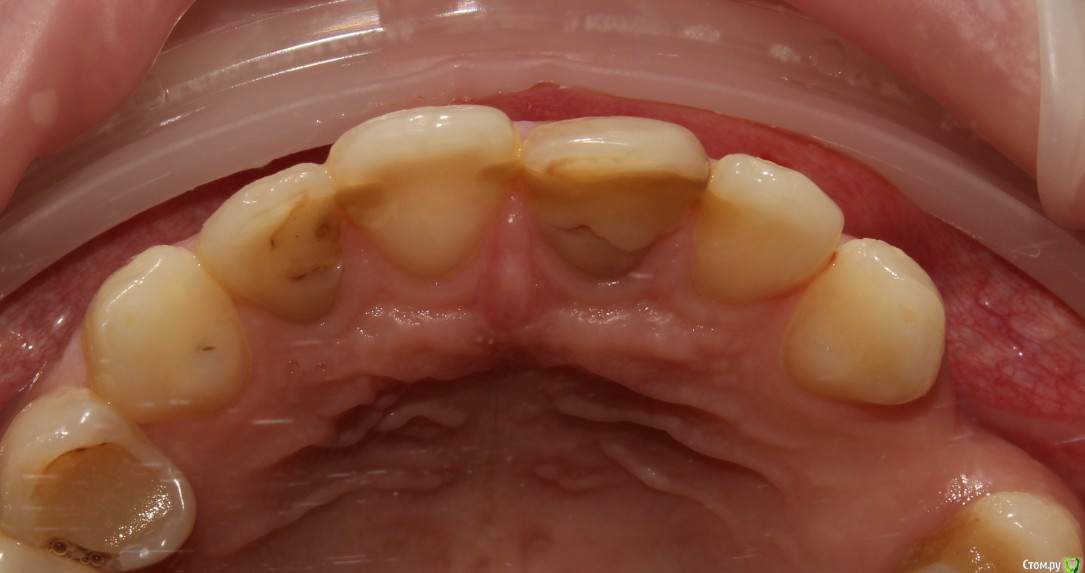

Рустам Опубликовано 4 ноября, 2016 Поделиться Опубликовано 4 ноября, 2016 Добрый вечер коллеги! Вчера обратилась пациентка (19 лет) с жалобой на подвижность коронки 1.1 зуба.Коронку убрал, скол достаточно глубоко (2-3мм ниже уровня десны), в зоне БШ. Удлинение во фронте не вариант на мой взгляд. Феррул не получить. Имплантолог ввиду возраста в имплантации отказывает.Пока сделал временный зуб на униметрике. КТ пока не делали. Записал на повторную консультацию. Как бы вы поступили в данной ситуации Ссылка на комментарий

229KAMA Опубликовано 4 ноября, 2016 Поделиться Опубликовано 4 ноября, 2016 Возможно вы не так выразились но коронки ни на одном из представленных снимков я неувидел.Теперь чтобы сделал я , учитывая гигиену по снимкам и количество зубов и качество пломб предположу как и уменя в госе я бы поработал "спасателем" как обычно за неимением финансовой возможности у больного , а может и особого желания заниматься зубами.1-подрезалбы десну по вестибулярке.2-времен.востан.коронк. часть зуба через анкерный штифт.(хорошо его зафиксир)чтобы попробовать немного вытянуть коронарно.(потреб времен.конечно и за свой счет ну хотябы частично.)3-после того как зуб перем корон.поработать с десной (может и с биологической шириной) по вестибулярке для того чтобы спрогнозировать минималный ферул. Ну тоже часть финанс нагр на мне.4-дальше если ферул получил то ВКВ и далее как обычно коронк.Да знаю нормальный врач сразу мне СКАЖЕТ что все это мартышкин труд надо ВСЕ как положенно , удалить может одномоментно винт и т.д.Но мне часто приходиться пахожие ситуации разруливать и зная как правильно НАДО , по обстоятельства разным приходиться становиться "спасателем" всегда заранее поциентам обьясняю что это не по протоколу. Только после этого пытаюсь оттянуть смертный приговор зуба. Некоторые возврашаются накопив средства чобы все сделать правильно и меня это радует , что кто то правильно понял мою информацию как надо правильно. Както так действую. 1 Ссылка на комментарий

voff Опубликовано 7 ноября, 2016 Поделиться Опубликовано 7 ноября, 2016 Я бы сделал временно-долговременно мк на вкв. И сказал, что рот весь в г...не, если не научитесь чистить зубы- импланта не видать. У меня таких пацев через одного. 4 Ссылка на комментарий